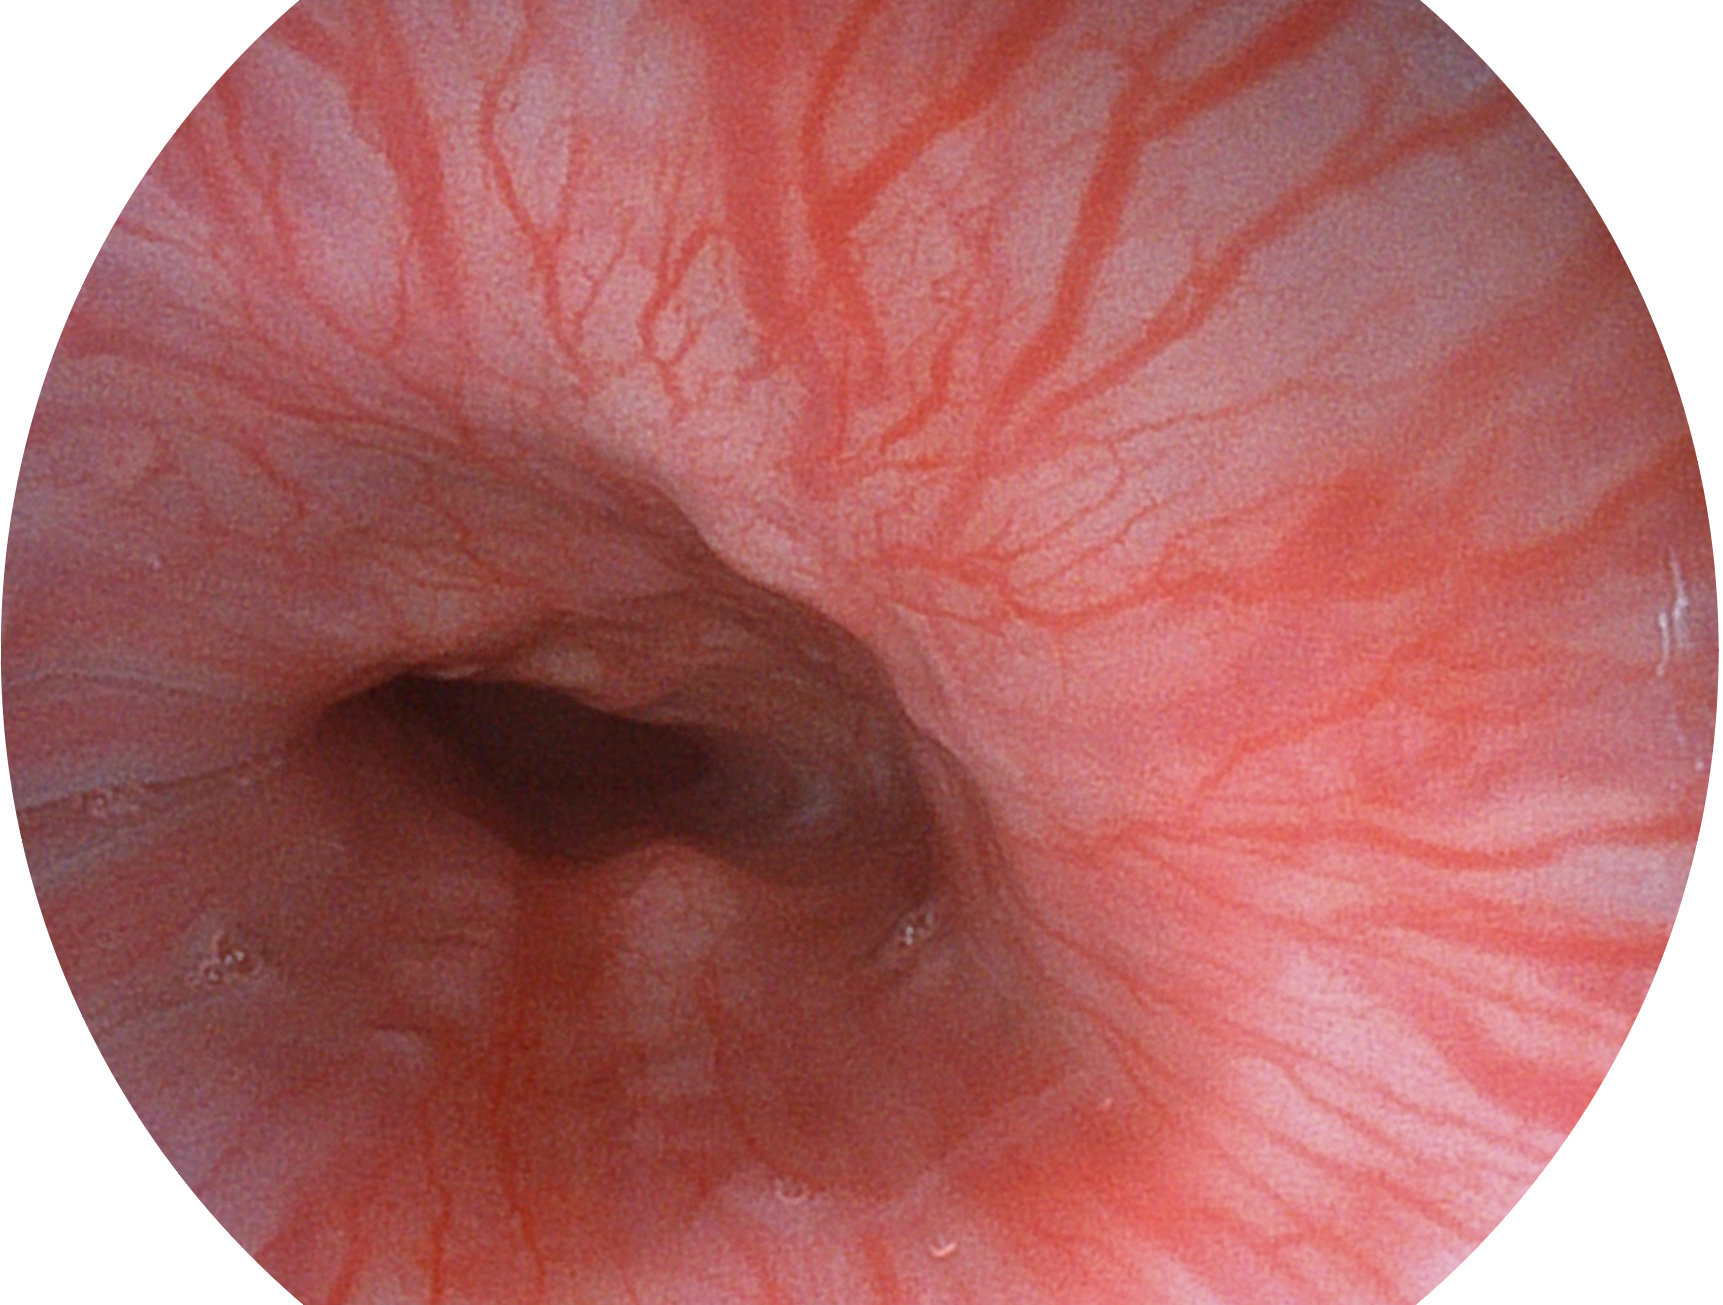

与上一代VIST相比,摒弃了滤光转轮而直接采用光谱组合的方案,加入了血红蛋白吸收高峰与次高峰的蓝紫光和绿光光谱,更有利于黏膜血管吸收,突显浅表层血管和中层血管的对比度,因而具备更高的图像对比度,近景观察时,有助于微细结构变化及病灶边界的观察。

• 白光图像 VIST图像